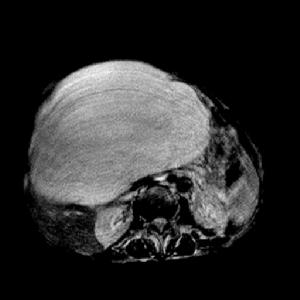

巨大肝囊腫出血(1)巨大肝囊腫:少數肝囊腫生長速度較快,當囊腫直徑超過10厘米,稱之為巨大肝囊腫。近年來,有採用超聲引導下進行囊腫穿刺抽液,囊腔內注入適量無水酒精,可使囊腔閉合;單發性巨大囊腫也可考慮切除;多發性囊腫可考慮部分肝切除術。

巨大非寄生蟲性肝囊腫2.單發性囊腫直徑5~10cm者或多發性肝囊腫,有2個直徑>5cm者,可考慮手術治療。有腹部包塊、疼痛或壓迫症狀明顯,或有併發症時,應考慮手術治療。